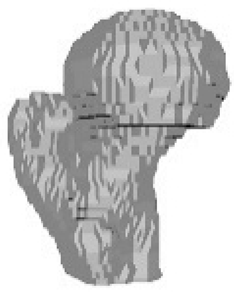

5.2. Comparison and Similarity of 3D Reconstruction Images

| Isometric View of the Left Femur | Ground Truth and Predicted Results of the Left Femur under Dataset Category F-I | |||||

|  | Front | Left | Rear | Right | Top | Bottom |

| Ground Truth |  |  |  |  |  |  |

| Prediction |  |  |  |  |  |  |